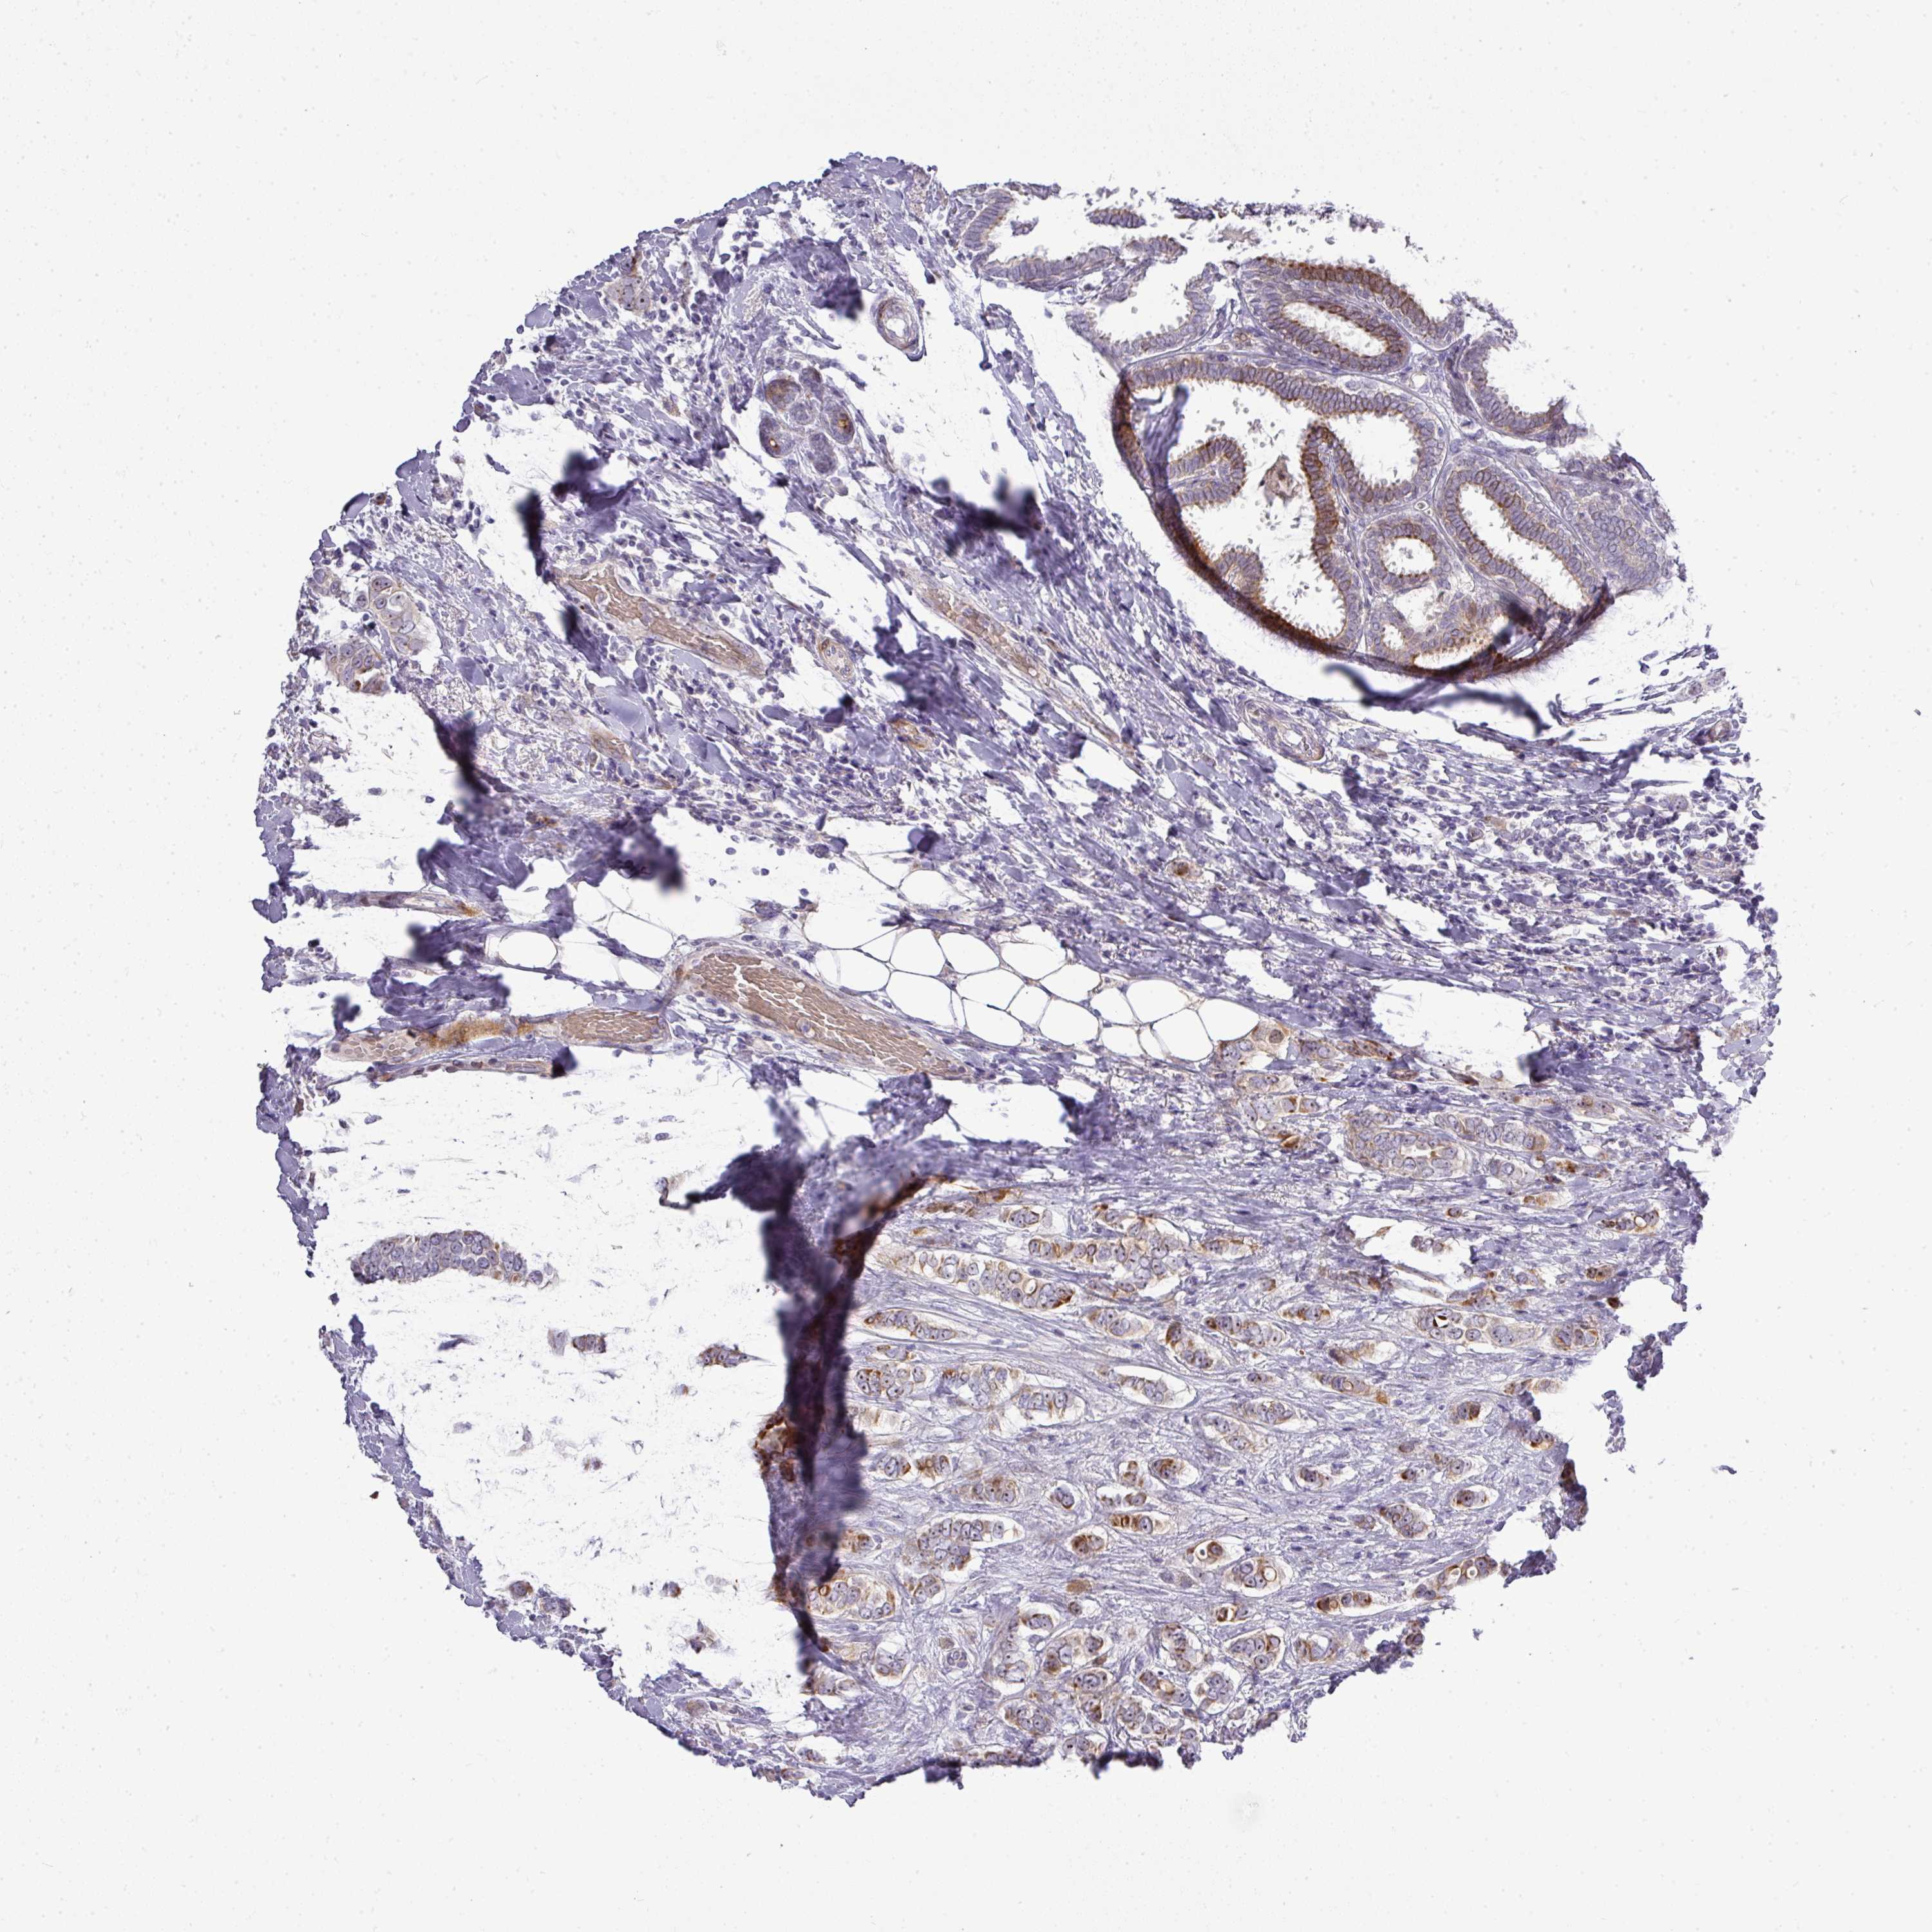

BRCA TCGA BRCA VALIDATION PROTEIN EXPRESSION

ANTIBODIES

AND

VALIDATION